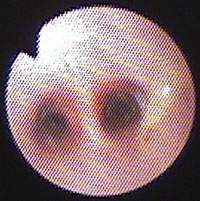

気管支鏡検査:第13病日に行った。肉眼所見で、可視範囲の気管支粘膜に軽度浮腫あり、気管分岐部と左右主気管支内に大きな黄色粘稠分泌物がみられた(図10)。LB1V1末梢のブラシ擦過標本の細胞診にて粘液、気管線毛上皮細胞、好酸球、リンパ球、好中球がみられ(図11左)、培養では陰性であった。BAL[RB3, 10ml×3, 回収率72%]では好酸球数の著しい増加(51.25%)とマクロファージの軽度活性化がみられ、培養にて細菌も真菌も検出されなかった。

図10 症例3の気管支鏡検査所見。気管分岐部に大きな黄色粘稠分泌物がみられた(写真右側)。他にも同様な粘稠分泌物が大量に気道壁に付着していた。